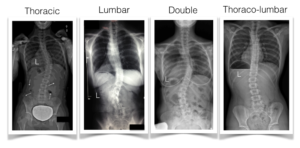

Scoliosis Curve Patterns – 4 Most Common Types